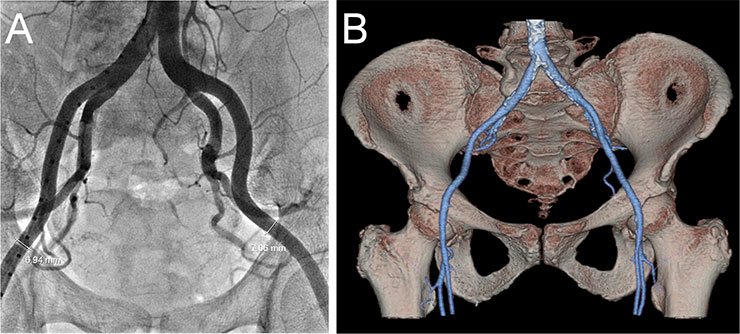

Figure 6

Screening of the iliofemoral arteries by fluoroscopy (A) and CT angiography (B).

Screening of iliofemoral access is usually accomplished using fluoroscopic angiography and/or CT angiography (fig. 6 ). Several protocols have been developed to reduce the amount of contrast dye required for CT scans in patients with reduced renal function [69, 70]. Current sheaths used for TAVI are 30–35 cm long, have an inner diameter of 14–20 French and an outer diameter of 5.9–7.8 mm. However, there are some exceptions. Following the slogan “think big”, the larger 22–24 F sheaths are still required for TAVI in the USA. There are several expandable sheaths which are introduced in a low profile configuration reducing the risk of iliofemoral injury. The Edwards expandable introducer sheath (Edwards Lifesciences, Irvine, CA) has a compliant seam that allows transient expansion as the delivery catheter is passed through it [71]. After passage of the prosthesis the sheath contracts to some degree towards its unexpanded size. The SoloPath sheath (Onset Medical Corporation, Irvine, CA) is a balloon expandable sheath that is inserted in its unexpanded state with an outer diameter of only 4.3 mm, facilitating delivery through difficult anatomy. A balloon is then inflated to expand the sheath and reach the intended internal diameter of 18–21 F.